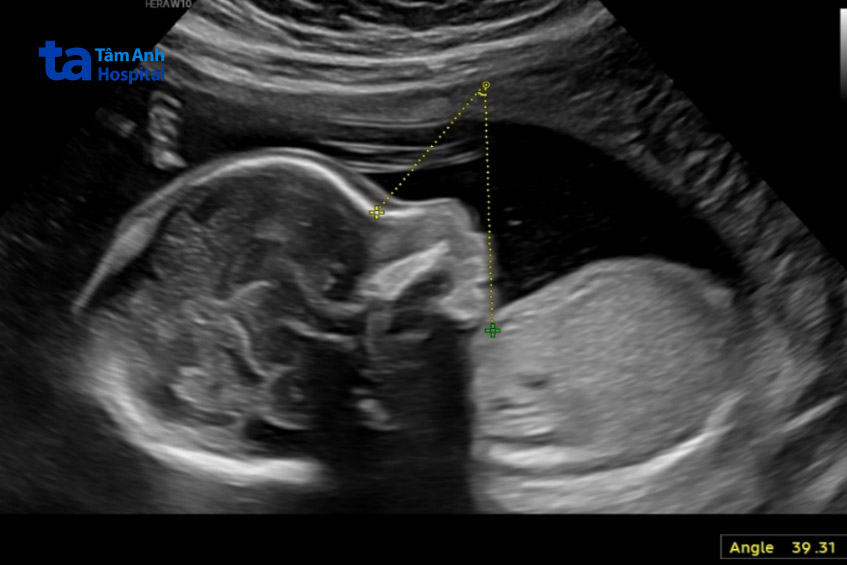

BS.CKI Nguyễn Thị Mộng Nghi, Trung tâm Y học bào thai, Bệnh viện Đa khoa Tâm Anh TP.HCM, siêu âm ghi nhận thai nhi cằm nhỏ, mũi khoằm (đầu mũi nhọn và cong xuống dưới), chưa thấy dấu hiệu bàn tay mở trong quá trình khảo sát. Các bất thường hệ thần kinh bao gồm thiểu sản thể chai (cấu trúc nối hai bán cầu đại não), rãnh Sylvius (nằm ở mặt ngoài của bán cầu đại não, ngăn cách thùy thái dương với thùy trán, thùy đỉnh) và rãnh đỉnh chẩm (rãnh ngăn cách thùy đỉnh và thùy chẩm) nông so với tuổi thai.

Thai nhi còn có bất thường tim cung động mạch chủ sang phải, tức là cung động mạch chủ (đoạn động mạch chủ từ tim, phân nhánh để cấp máu cho đầu, cổ và chi trên) đi về phía bên phải của khí quản và thực quản, thay vì bên trái như bình thường.